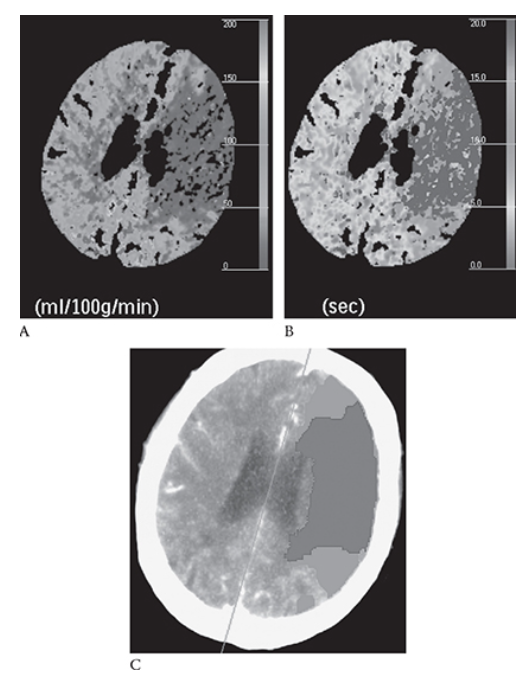

What is A

Ischemic Stroke. Same patient as in Figure 5 with the left MCA stroke. Shows decreased cerebral perfusion to this area (blue) Mean transit time is prolonged (blue)

What is B

Ischemic Stroke. Same patient as in Figure 5 with the left MCA stroke. Shows decreased cerebral perfusion to this area (blue) In image

What is C

Ischemic Stroke. Same patient as in Figure 5 with the left MCA stroke. Shows decreased cerebral perfusion to this area (blue) red represents an infarct; green represents the penumbra of threatened (at risk) ischemic brain that may potentially be saved with an intervention. (see Color Insert).

Ischemic Stroke. NECT axial image shows a hyperdense left MCA. There is decreased attenuation in the left MCA territory

Ischemic Stroke. NECT axial image in the same patient and loss of the gray with differentiation resulting in the “insular ribbon sign.”